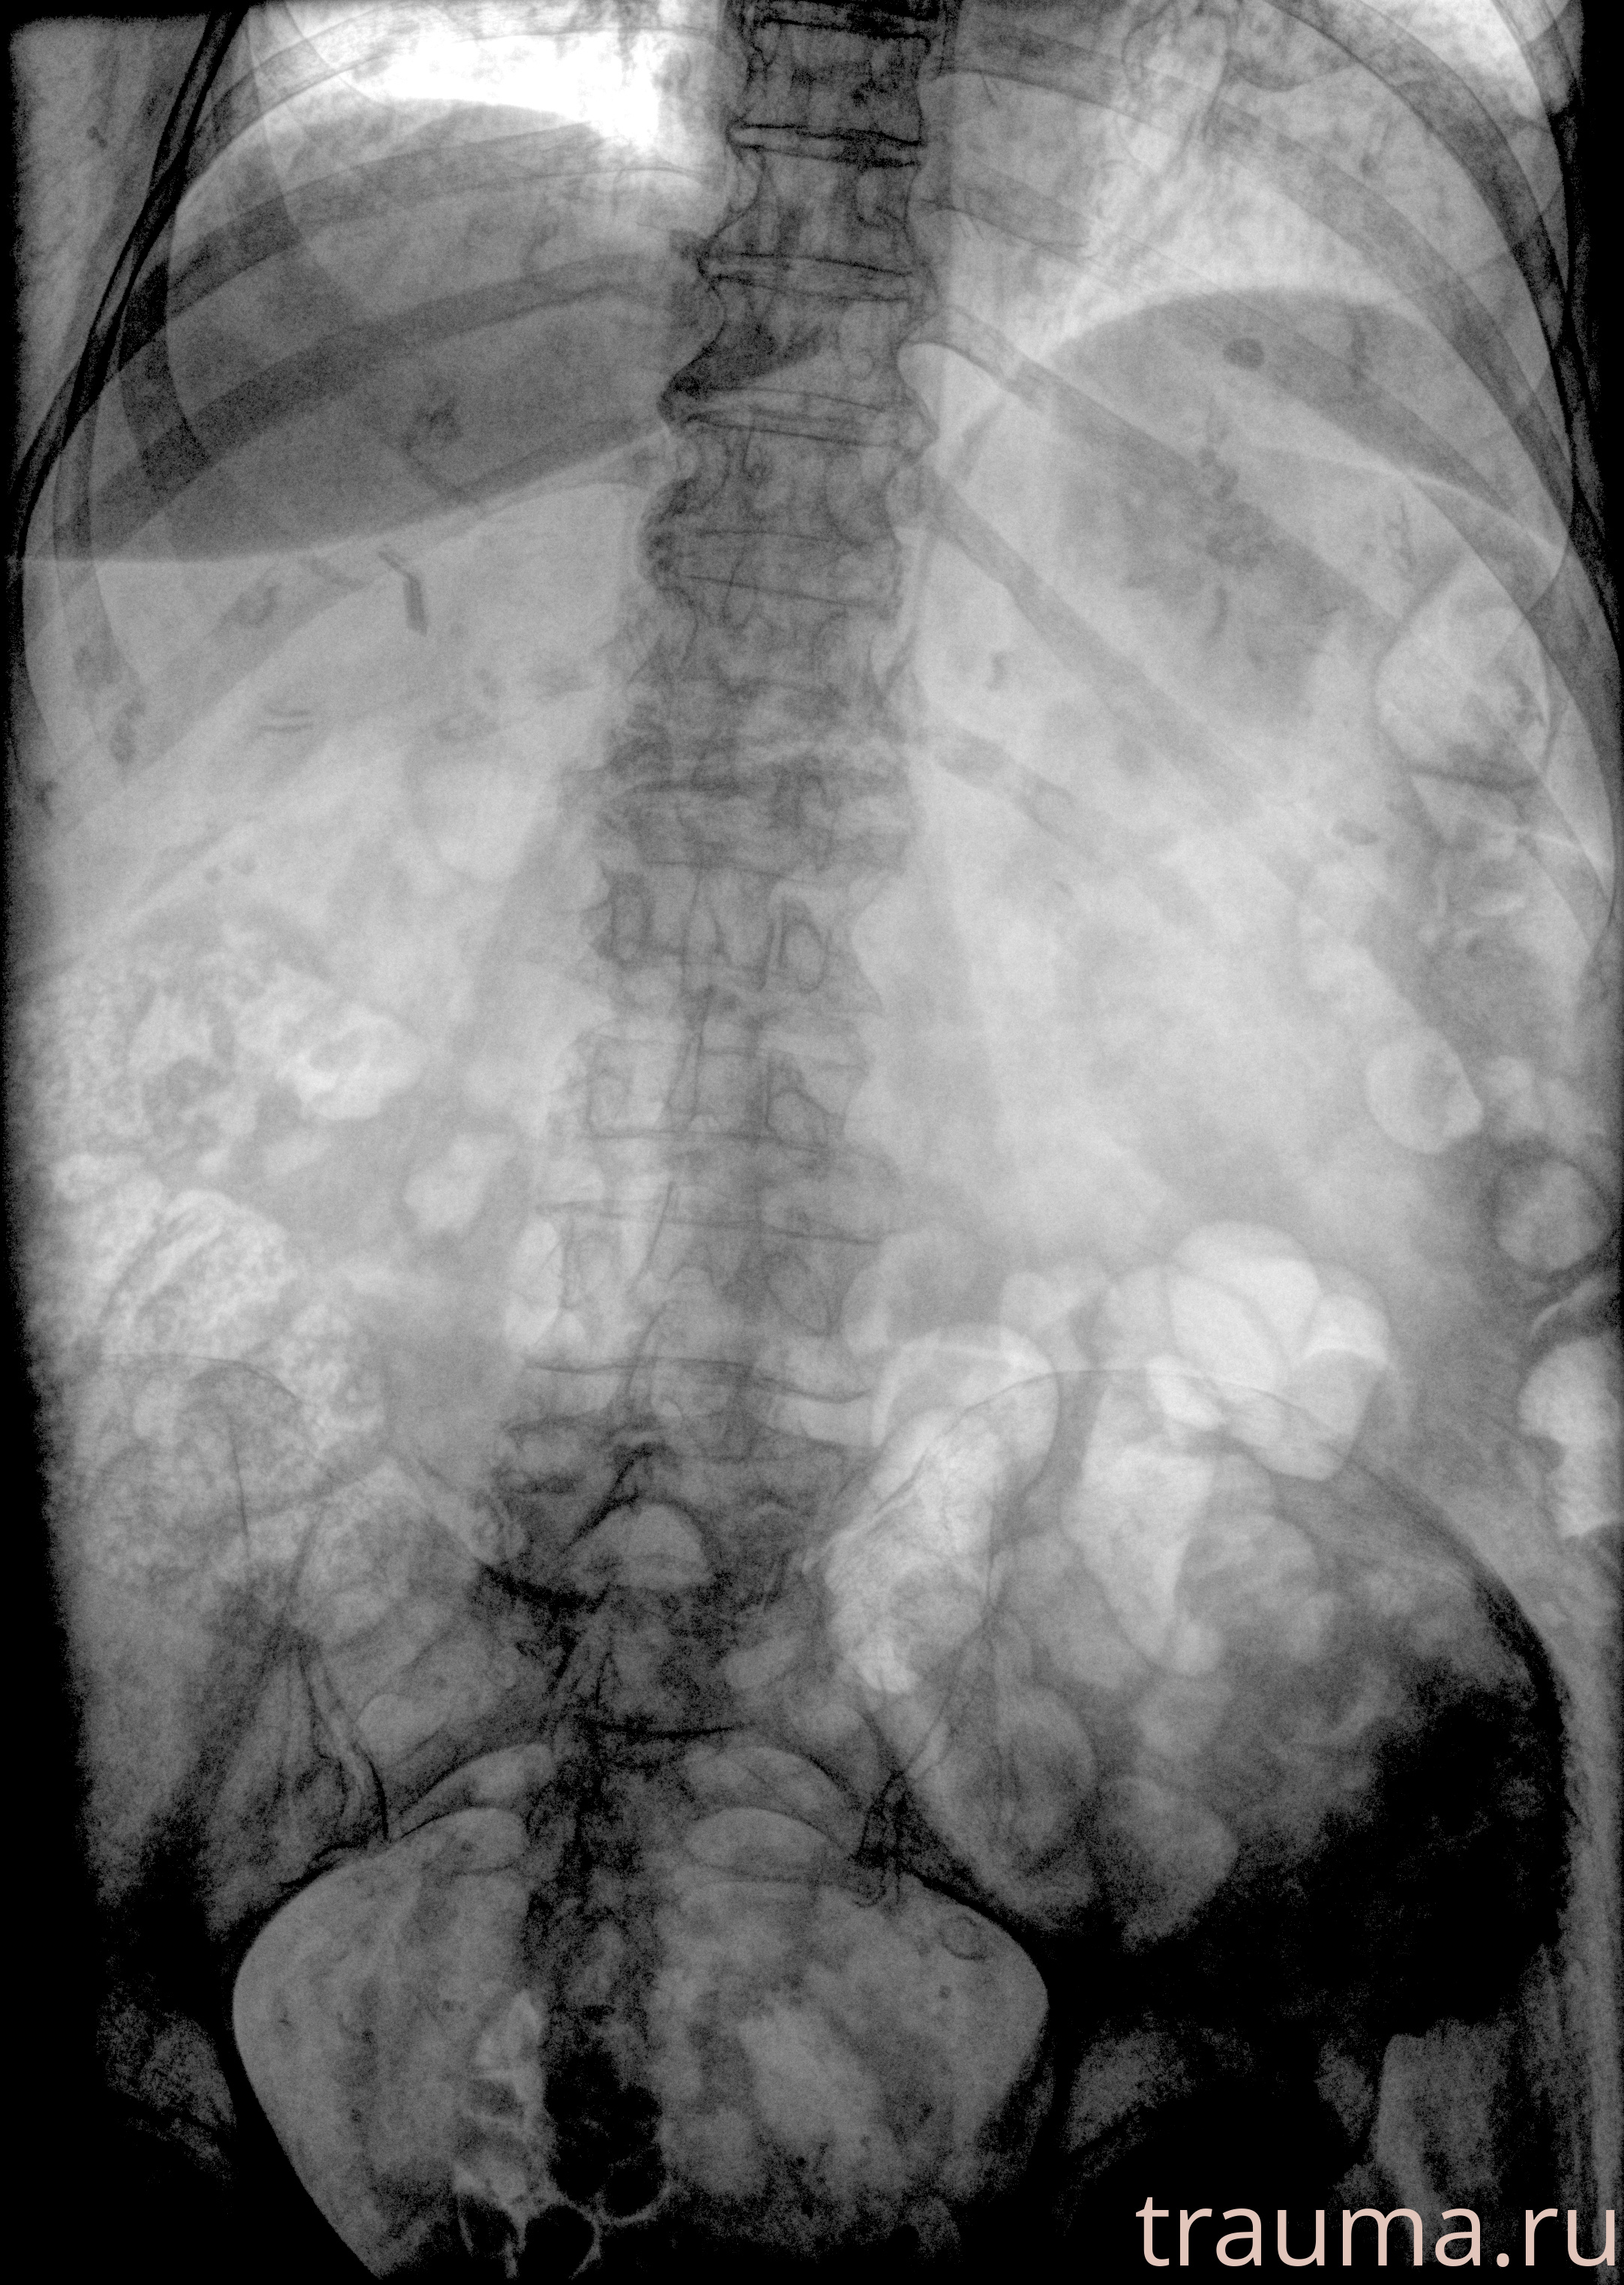

Рентгенограммы

Рентген на дому: по вашему адресу приезжает врач-рентгенолог, травматолог-ортопед с мобильным рентгеновским аппаратом, проводит диагностику травмы или заболевания, делает необходимые рентгенограммы, дает рекомендации по дальнейшему лечению. Получить качественные снимки в домашних условиях возможно благодаря уникальной методике, разработанной МосРентген Центром для института  Склифосовского